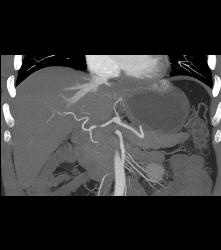

Multifocal Hepatocellular Carcinoma (Hepatoma)